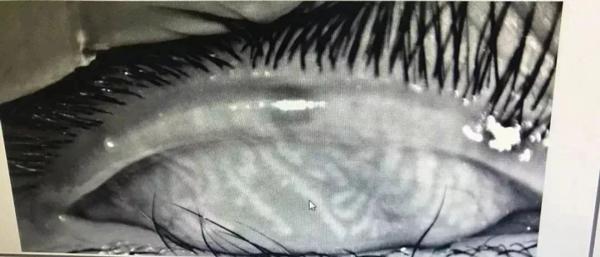

Các tuyến mebomius của cậu bé Tiểu Tân bị rối loạn.

Bác sĩ Hồng Nam khoa Nhãn khoa, Bệnh viện liên kết số 1 với Đại học Y khoa Chiết Giang sau khi kiểm tra mắt của cậu bé rất sốc. Bởi các tuyến meibomius của cậu bé 11 tuổi này còn tệ hơn so với những người ở độ tuổi 50-60. Bác sĩ nói rằng Tiểu Tân đã bị rối loạn thị lực, chức năng tuyến meibomius nghiêm trọng, gây ra hội chứng khô mắt.

Có khoảng 32 tuyến meibomius trên mí mắt của người bình thường, được sắp xếp thành các đường thẳng đứng song song, tiết ra dầu để làm ẩm nhãn cầu. Tuy nhiên, với Tiểu Tân, các tuyến meibomius của cậu bé đã bị "xoắn" thành một mạng lưới, không còn rõ ràng, giống như mắt của người trung niên và người cao tuổi nhưng ở mức độ còn tồi tệ hơn. Vì vậy, mắt cậu bé mới bị đau nhói, nóng rát và không thể mở nổi mắt. Điều đáng buồn hơn nữa khi bác sĩ nói rằng khó có thể khôi phục hoàn toàn chức năng tuyến meibomius của Tiểu Tân.